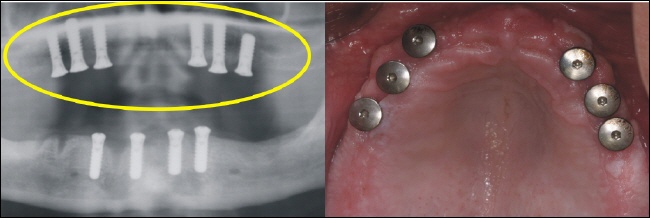

Sechs strategisch günstig positionierte Implantate wurden im Oberkiefer eingebracht, um nach der Einheilung optimalen Halt für die Prothese zu gewährleisten (gelber Kreis im Röntgenbild). |

Im Unterkiefer können die vier Implantate (Standardversorgung) im vorderen Kieferbereich eingebracht werden (gelber Kreis im Röntgenbild). |